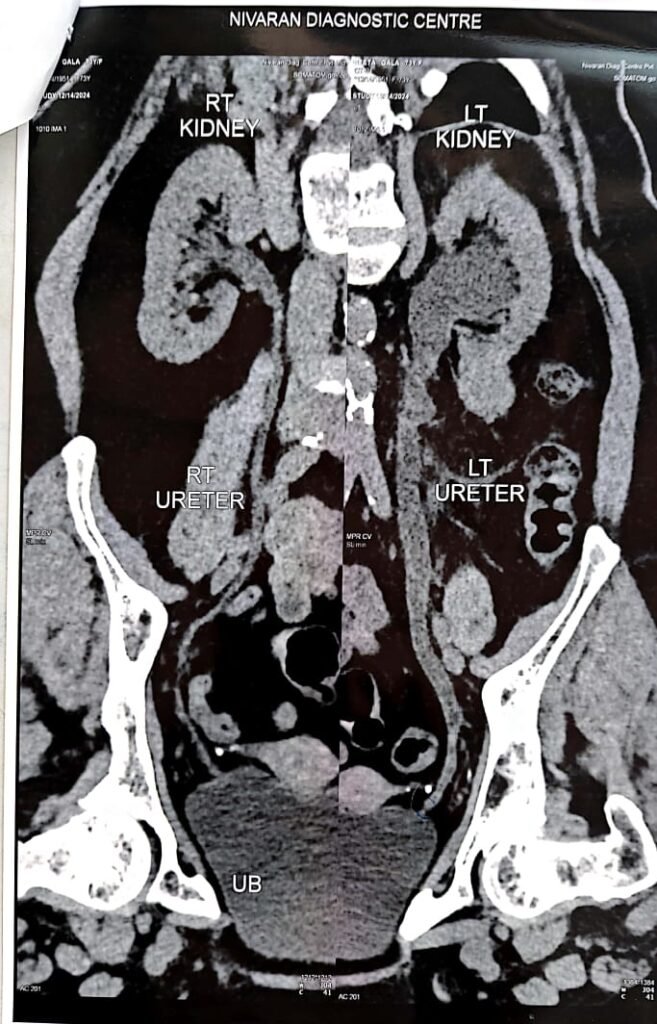

The patient was experiencing severe flank pain, urinary disturbances, and hydronephrosis (swelling of the kidney due to urine blockage). A CT Urogram confirmed narrowing of the ureter.

The patient presented with symptoms of flank pain, hydronephrosis, and urinary disturbances. Imaging (CT Urogram) confirmed the presence of a ureteric narrowing, leading to partial or complete obstruction.

Follow-up imaging showed significant improvement in the ureteric stricture.